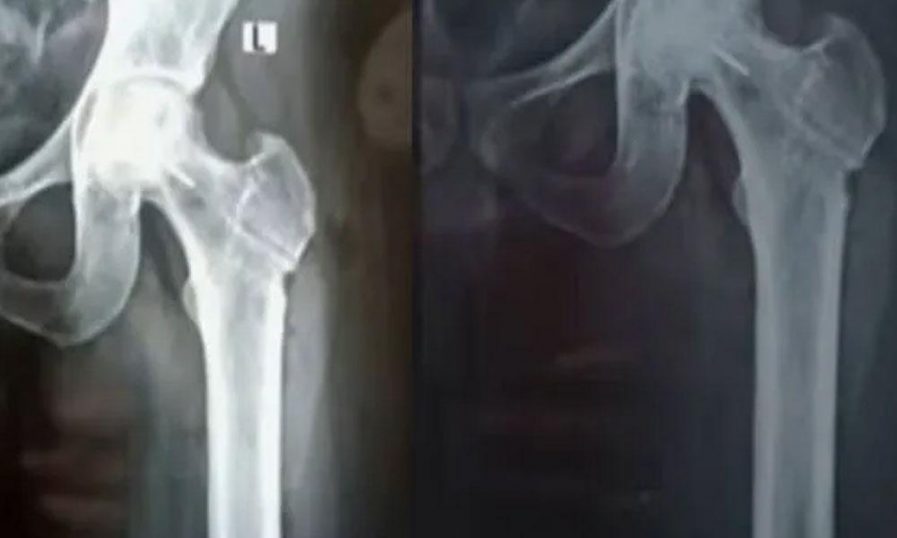

രക്തയോട്ടം കൂട്ടാന് ഇടുപ്പ് എല്ലിലായിരുന്നു ശസ്ത്രക്രിയ നടത്തിയിരുന്നത്

തിരുവനന്തപുരം| പാളയത്തെ ജൂബിലി മെമ്മോറിയല് ആശുപത്രിയില് ഗുരുതര ചികിത്സാ പിഴവെന്ന് പരാതി. ശസ്ത്രക്രിയയ്ക്കിടെ ലോഹഭാഗം എല്ലില് തുളഞ്ഞുകയറുകയായിരുന്നു. മലയിന്കീഴ് സ്വദേശി ജിജിന് ജോസിനാണ് ദുരനുഭവം ഉണ്ടായത്. രക്തയോട്ടം കൂട്ടാന് ഇടുപ്പ് എല്ലിലായിരുന്നു ശസ്ത്രക്രിയ നടത്തിയിരുന്നത്. ജിജിന്റെ പരാതിയില് കന്ോണ്മെന്റ് പോലീസ് കേസെടുത്തിട്ടുണ്ട്.

കഴിഞ്ഞ നവംബര് 17 നായിരുന്നു ശസ്ത്രക്രിയ നടന്നത്. ശസ്ത്രക്രിയയ്ക്ക് ശേഷം എല്ലിന്റെ ഭാഗത്തെ വേദന മാറാതായതോടെയാണ് ജിജിന് വീണ്ടും ആശുപത്രിയില് എത്തിയത്. പിന്നീട് നടത്തിയ പരിശോധനയിലാണ് ശസ്ത്രക്രിയക്കിടെ ഡ്രില് ബിറ്റ് ഒടിഞ്ഞു കയറുകയായിരുന്നു എന്ന് മനസിലാക്കിയത്. ലോഹ കഷണം നീക്കം ചെയ്യാനാകില്ലെന്നും അത് എല്ലിന്റെ ഭാഗമായി കഴിഞ്ഞെന്നുമായിരുന്നു ഡോക്ടര്മാര് അറിയിച്ചിരുന്നത്. ഈ സാഹചര്യത്തിലാണ് പരാതിയുമായി ജിജിന് എത്തിയത്.